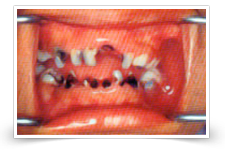

1.RAMPANT Caries {decay}

2. Nursing caries {decay}

It is the form of decay that affects infants and toddlers. This has been observed in children as young as 12 months of age.

If there is stagnation of milk or sweetened juices etc. around the teeth for long periods of time, the natural sugar in milk is converted into acid by bacteria and decay begins. This especially occurs in cases of long feeds or feeds during sleep-time. This type of decay spreads quickly and affects a lot of teeth. Weaning should be complete by approximately 18 months of age. Hence, it is advisable to avoid nursing the child to sleep or bottle-feeding the child when it is asleep. At these times water can be used as a pacifier.